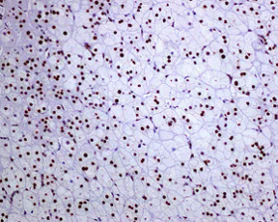

Immunohistochemistry (Formalin/PFA-fixed paraffin-embedded sections) - Anti-FTO antibody [EPR6894] - BSA and Azide free (AB240021)

Immunohistochemical staining of paraffin embedded human hepatocellular carcinoma with purified ab126605 at a working dilution of 1 in 500. The secondary antibody used is a HRP polymer for rabbit IgG. The sample is counter-stained with hematoxylin. Antigen retrieval was perfomed using Tris-EDTA buffer, pH 9.0. PBS was used instead of the primary antibody as the negative control, and is shown in the inset.

This data was developed using the same antibody clone in a different buffer formulation containing PBS, BSA, glycerol, and sodium azide (ab126605).